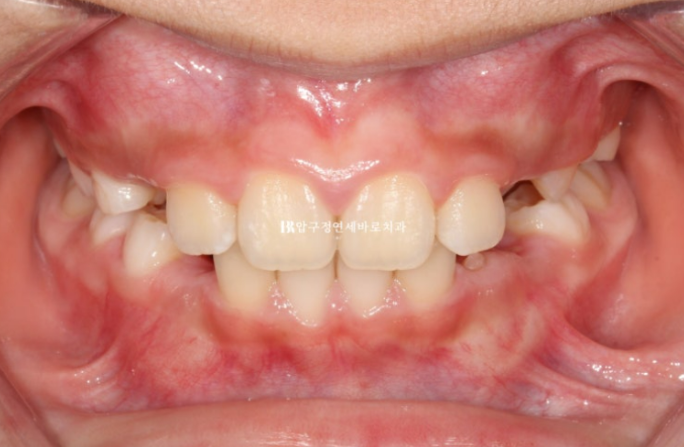

23.09

맞아진 위 아래 앞니 중심선과 개선된 과개교합

돌출된 앞니도 제자리로 들어갔습니다.